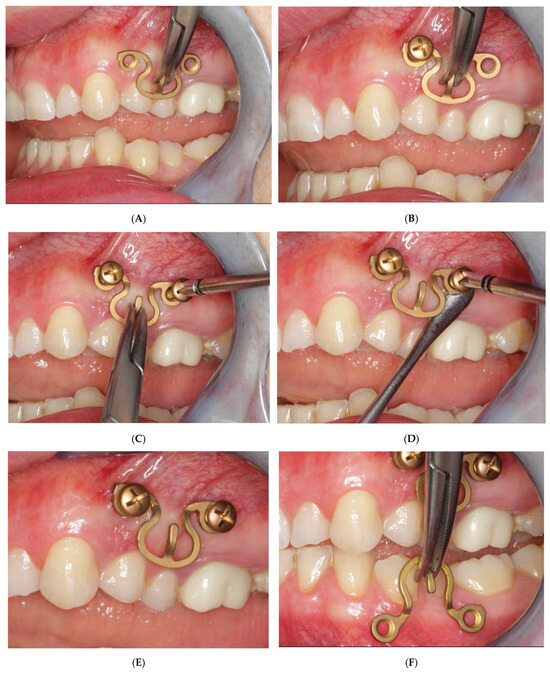

3.2. Matrix WaveTM Plate MMF System—Mode of Application